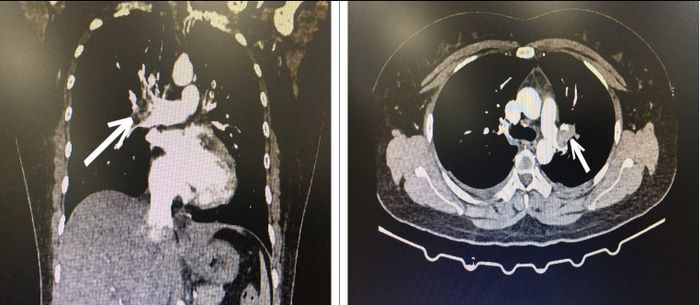

Bác sĩ cấp cứu hướng chẩn đoán tới bệnh thuyên tắc động mạch phổi cấp và quyết định cho chụp CT ngực có tiêm thuốc cản quang, kết quả là hình ảnh huyết khối động mạch phổi 2 bên.

Bệnh nhân đã được chẩn đoán xác định là huyết khối thuyên tắc động mạch phổi cấp tính do lạm dụng thuốc tránh thai. Người phụ nữ này được điều trị tại khoa Hồi sức tim mạch theo phác đồ chống đông, hỗ trợ hô hấp. Bệnh tiến triển tốt, sau 7 ngày, bệnh nhân đã hết khó thở, toàn trạng ổn định và được ra viện.

Hình ảnh CT lồng ngực bệnh nhân bị tắc động mạch phổi cấp tính